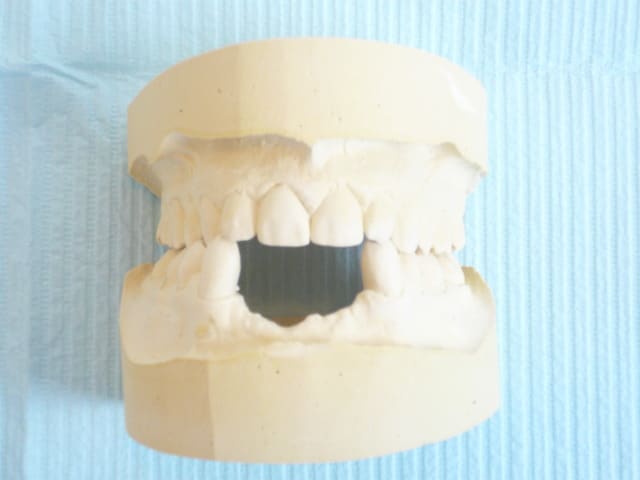

Comme c'est peut-être une patiente disons "spéciale", avant de me lancer dans quelquechose de délicat esthétiquement, je lui ferais un wax-up en "dur" résine et dent de PPA à l'image de ce qu'elle aura en bouche (prothèse sur pilotis ou PPA transvissée) afin de bien lui montrer le type de résultat obtenus avec ces prothèses là.

faut bien qu'elle sache le type de résultat prothétique.

çà va faire des implants de 10-11.5 mm avec une partie prothétique de 22-23 mm de haut! pourquoi pas alors 3 implants (32-42 et un médian pour soutenir toute cette structure qui va reconstituer à la fois dents mais aussi partie de crête résorbée)

faudrait voir aussi les rapports antéro-postérieurs des incisives